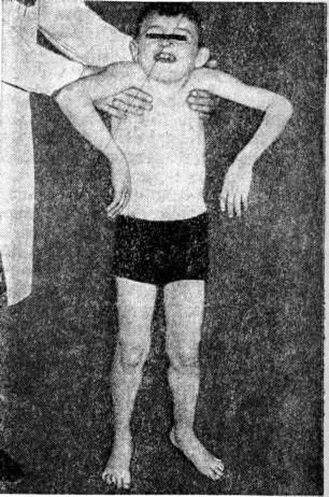

Ведущими симптомами заболеваний этой группы являются повышенная утомляемость и слабость мышц, симметричные мышечные атрофии, снижение или отсутствие сухожильных рефлексов. При отдельных формах заболевания отмечается псевдогипертрофия (рисунок 3), когда объем поражённых мышц увеличен, хотя сила их снижена так же, как при атрофии. При локализации миодистрофического процесса в области лица мимика больных становится бедной. Гипомимия приводит к характерному выражению лица — «миопатическое лицо». Следствием атрофии круговой мышцы рта является «поперечная улыбка». Губы утолщены и несколько вывернуты кнаружи — «губы тапира». На лбу отсутствуют морщины — симптом «полированного лба».

Поражение поперечнополосатых мышц глаз приводит к частичной или полной офтальмоплегии, птозу, экзофтальму, лагофтальму. Поражение мышц мягкого неба, глотки и гортани проявляется нарушением глотания и фонации. Симптомы поражения мышц плечевого пояса — ограничение объёма активных движений в проксимальных отделах рук, отставание лопаток от туловища — симптом «крыловидных лопаток» (рисунок 4), отсутствие сопротивления мышц плечевого пояса при поднимании больного за подмышки — симптом «свободных надплечий» (рисунок 5.); плечи больного поднимаются вверх, а голова как бы проваливается между ними. Атрофия длинных мышц спины и тазового пояса проявляется нарушением осанки и походки: выражен гипер лордоз позвоночника, голова несколько запрокинута назад, туловище при ходьбе ритмично раскачивается — «утиная походка». Затруднено поднимание по лестнице, вставание из сидячего положения. Для того чтобы принять вертикальное положение, больной вынужден прибегать к помощи рук, опираясь на соседние предметы или собственные бедра,— вставание «лесенкой» (симптом «лестницы» — рисунок 6, я, б, в). При атрофии косых мышц живота наблюдается симптом «осиной талии». Нарушение походки по типу «степпажа» или «петушиной походки» характерно для локализации миодистрофического процесса в мышцах голени и стопы. Поражение мышц приводит к ограничению подвижности суставов вплоть до образования контрактур. Присоединяющаяся, как правило, в поздней стадии заболевания легочно-сердечная недостаточность является следствием миодистрофического процесса в миокарде и дыхательной мускулатуре. При электромиографическом исследовании выявляют снижение амплитуды осцилляций, высокую частоту полифазных потенциалов, укорочение времени отдельных осцилляций.